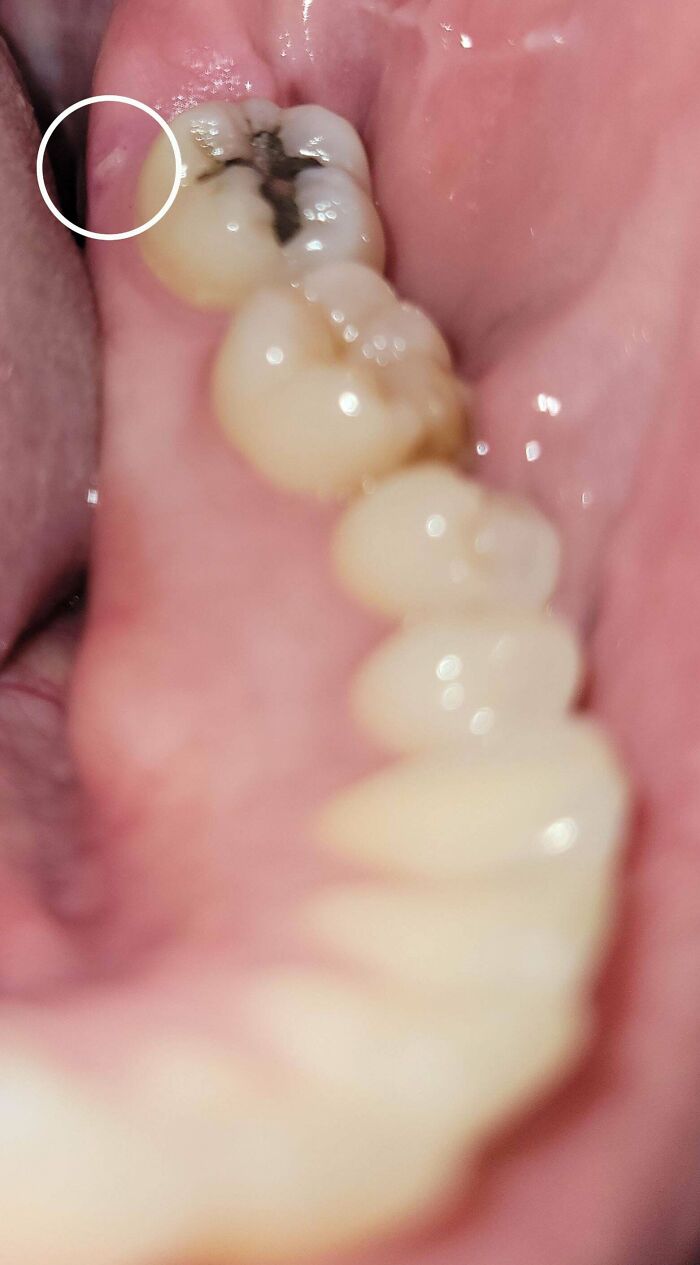

Un pequeño fragmento de hueso emergió 14 años después de la extracción de una muela del juicio.